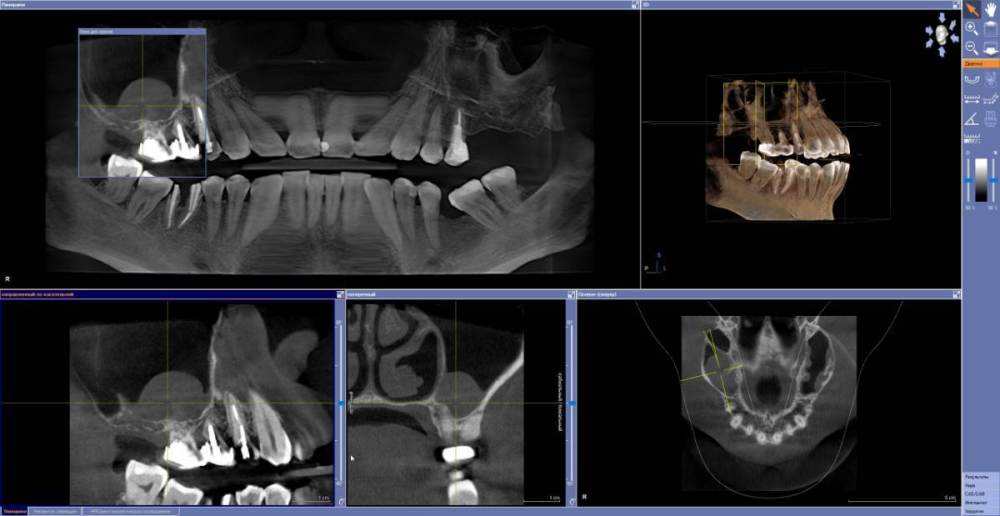

Есть вот такая ситуация  -  удалили летом 16,15. Пациентка пролечилась у ЛОР, сделали КТ вот перед новым годом - ситуация внутри гайморовой пазухи не изменилась (снимок КТ этот еще до удаления, но на новом все внутри так же, не прихватил с собой новое кт)

Сейчас необходимо провести открытый синуслифтинг в области (17) 16 (15). Вызывает опасения образование в пазухе - не помешает ли? Нужно ли убирать эту кисту или достаточно просто синуслифтинг провести?  Или это вообще не киста а разрастание слизистой?